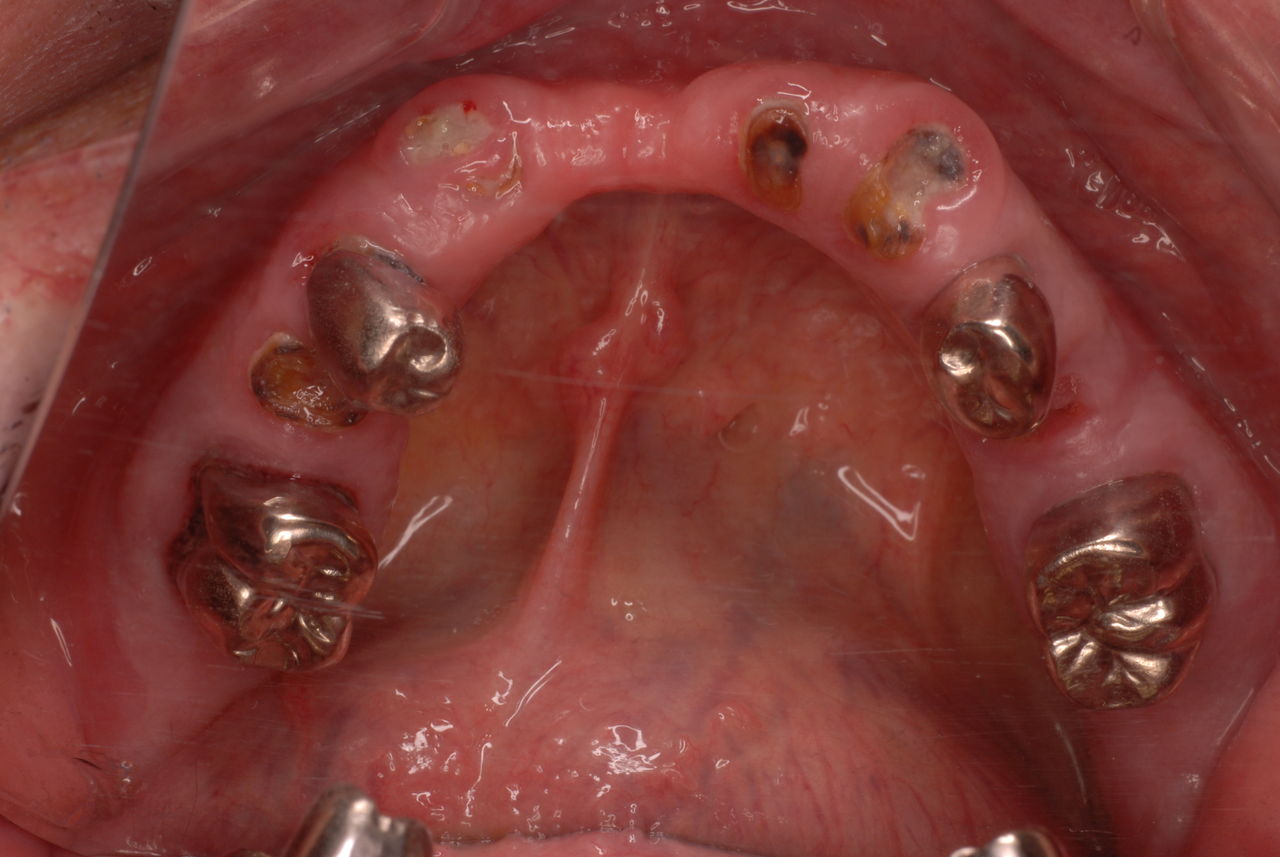

70代の患者ですが上の歯は残根一つ全て歯は無し。